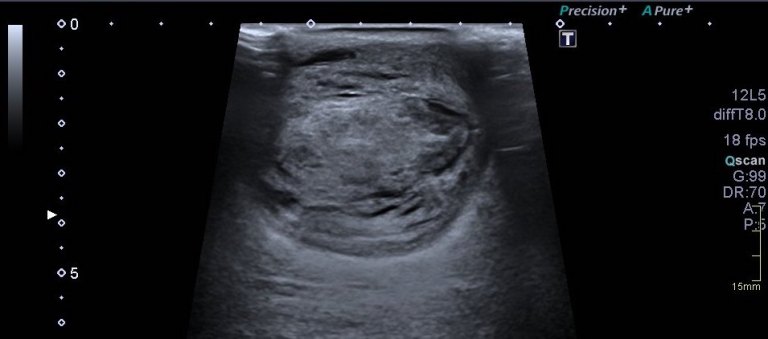

Se realiza estudio ecográfico de la «tumoración» que presenta el paciente la región postero interna de la pierna izquierda, se visualiza lesión heterogénea de 41 x 53 x 54 mm con áreas quísticas localizados sobre todo el tejido celular subcutáneo que presiona al gemelo medial, muy escasa vascularización, y áreas con sospecha de necrosis que en la ecografía se corresponden con imágenes de aspecto quístico.

Siempre es muy importante estudiar la patología en dos proyecciones, eje corto y eje largo. Medirlo y documentarlo muy muy bien. En caso de no usar pictograma, tenemos que escribir en la zona exacta donde se encuentra la lesión o la ecoestructura a estudio para que la radióloga sepa exactamente la localización.

En estos casos donde la figura patológica está muy a piel, o está muy superficial es imprescindible poner una buena capa de gel entre la piel y la sonda a fin de no presionar en exceso para no deformarla y así poder perder cierta información que puede ser relevante.

Imágenes ecografía: